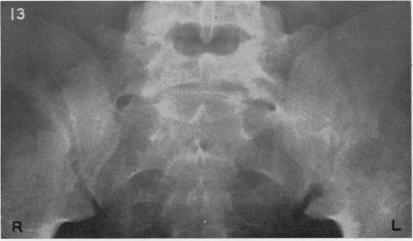

Sacro-ilitis in Still's disease.

Ann Rheum Dis. 1962 Jun;21(2):105-20. doi: 10.1136/ard.21.2.105.